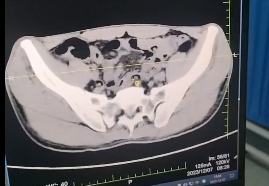

2023年12月4日晚上10时许,蚌埠市第四人民医院(市康复医院)急诊外科诊室进来一名患者,“医生,肚子突然痛的受不了”、“疼痛有2小时了”、“快点救救我”。急诊外科值班支永成主治医师立即上前,凭借丰富的临床经验,通过查体初步诊断:上消化道穿孔。立即行立位腹部平片+腹部CT检查提示:膈下游离气体,考虑上消化道穿孔。随后立即办理入院,在医院总值班石法荣主任协调下,功能科袁伟主任完善各项术前检查,同时麻醉科张建平主任及手术室护理团队在手术室立即做好了准备,随时准备手术。

急诊外科马夫锋副主任医师结合患者病情,体检及各项检查,明确患者为胃穿孔,通过阅片,确定穿孔位置在胃小弯。立即决定为患者行“腹腔镜下胃穿孔修补术”。术中探查与术前诊断一致,术中见:胃小弯及胆囊窝处大量脓性分泌物渗出,右肝周围见大量脓性液体,胃穿孔位置在胃小弯前壁,直径约0.8cm。在麻醉科及手术室护理团队的配合下,马夫锋副主任与支永成主治医师一起为患者行“腹腔镜下胃穿孔修补+腹腔冲洗引流术”,手术顺利,术后患者生命体征平稳,腹部疼痛明显好转,无明显不适,身体状况恢复良好。

术后复查结果